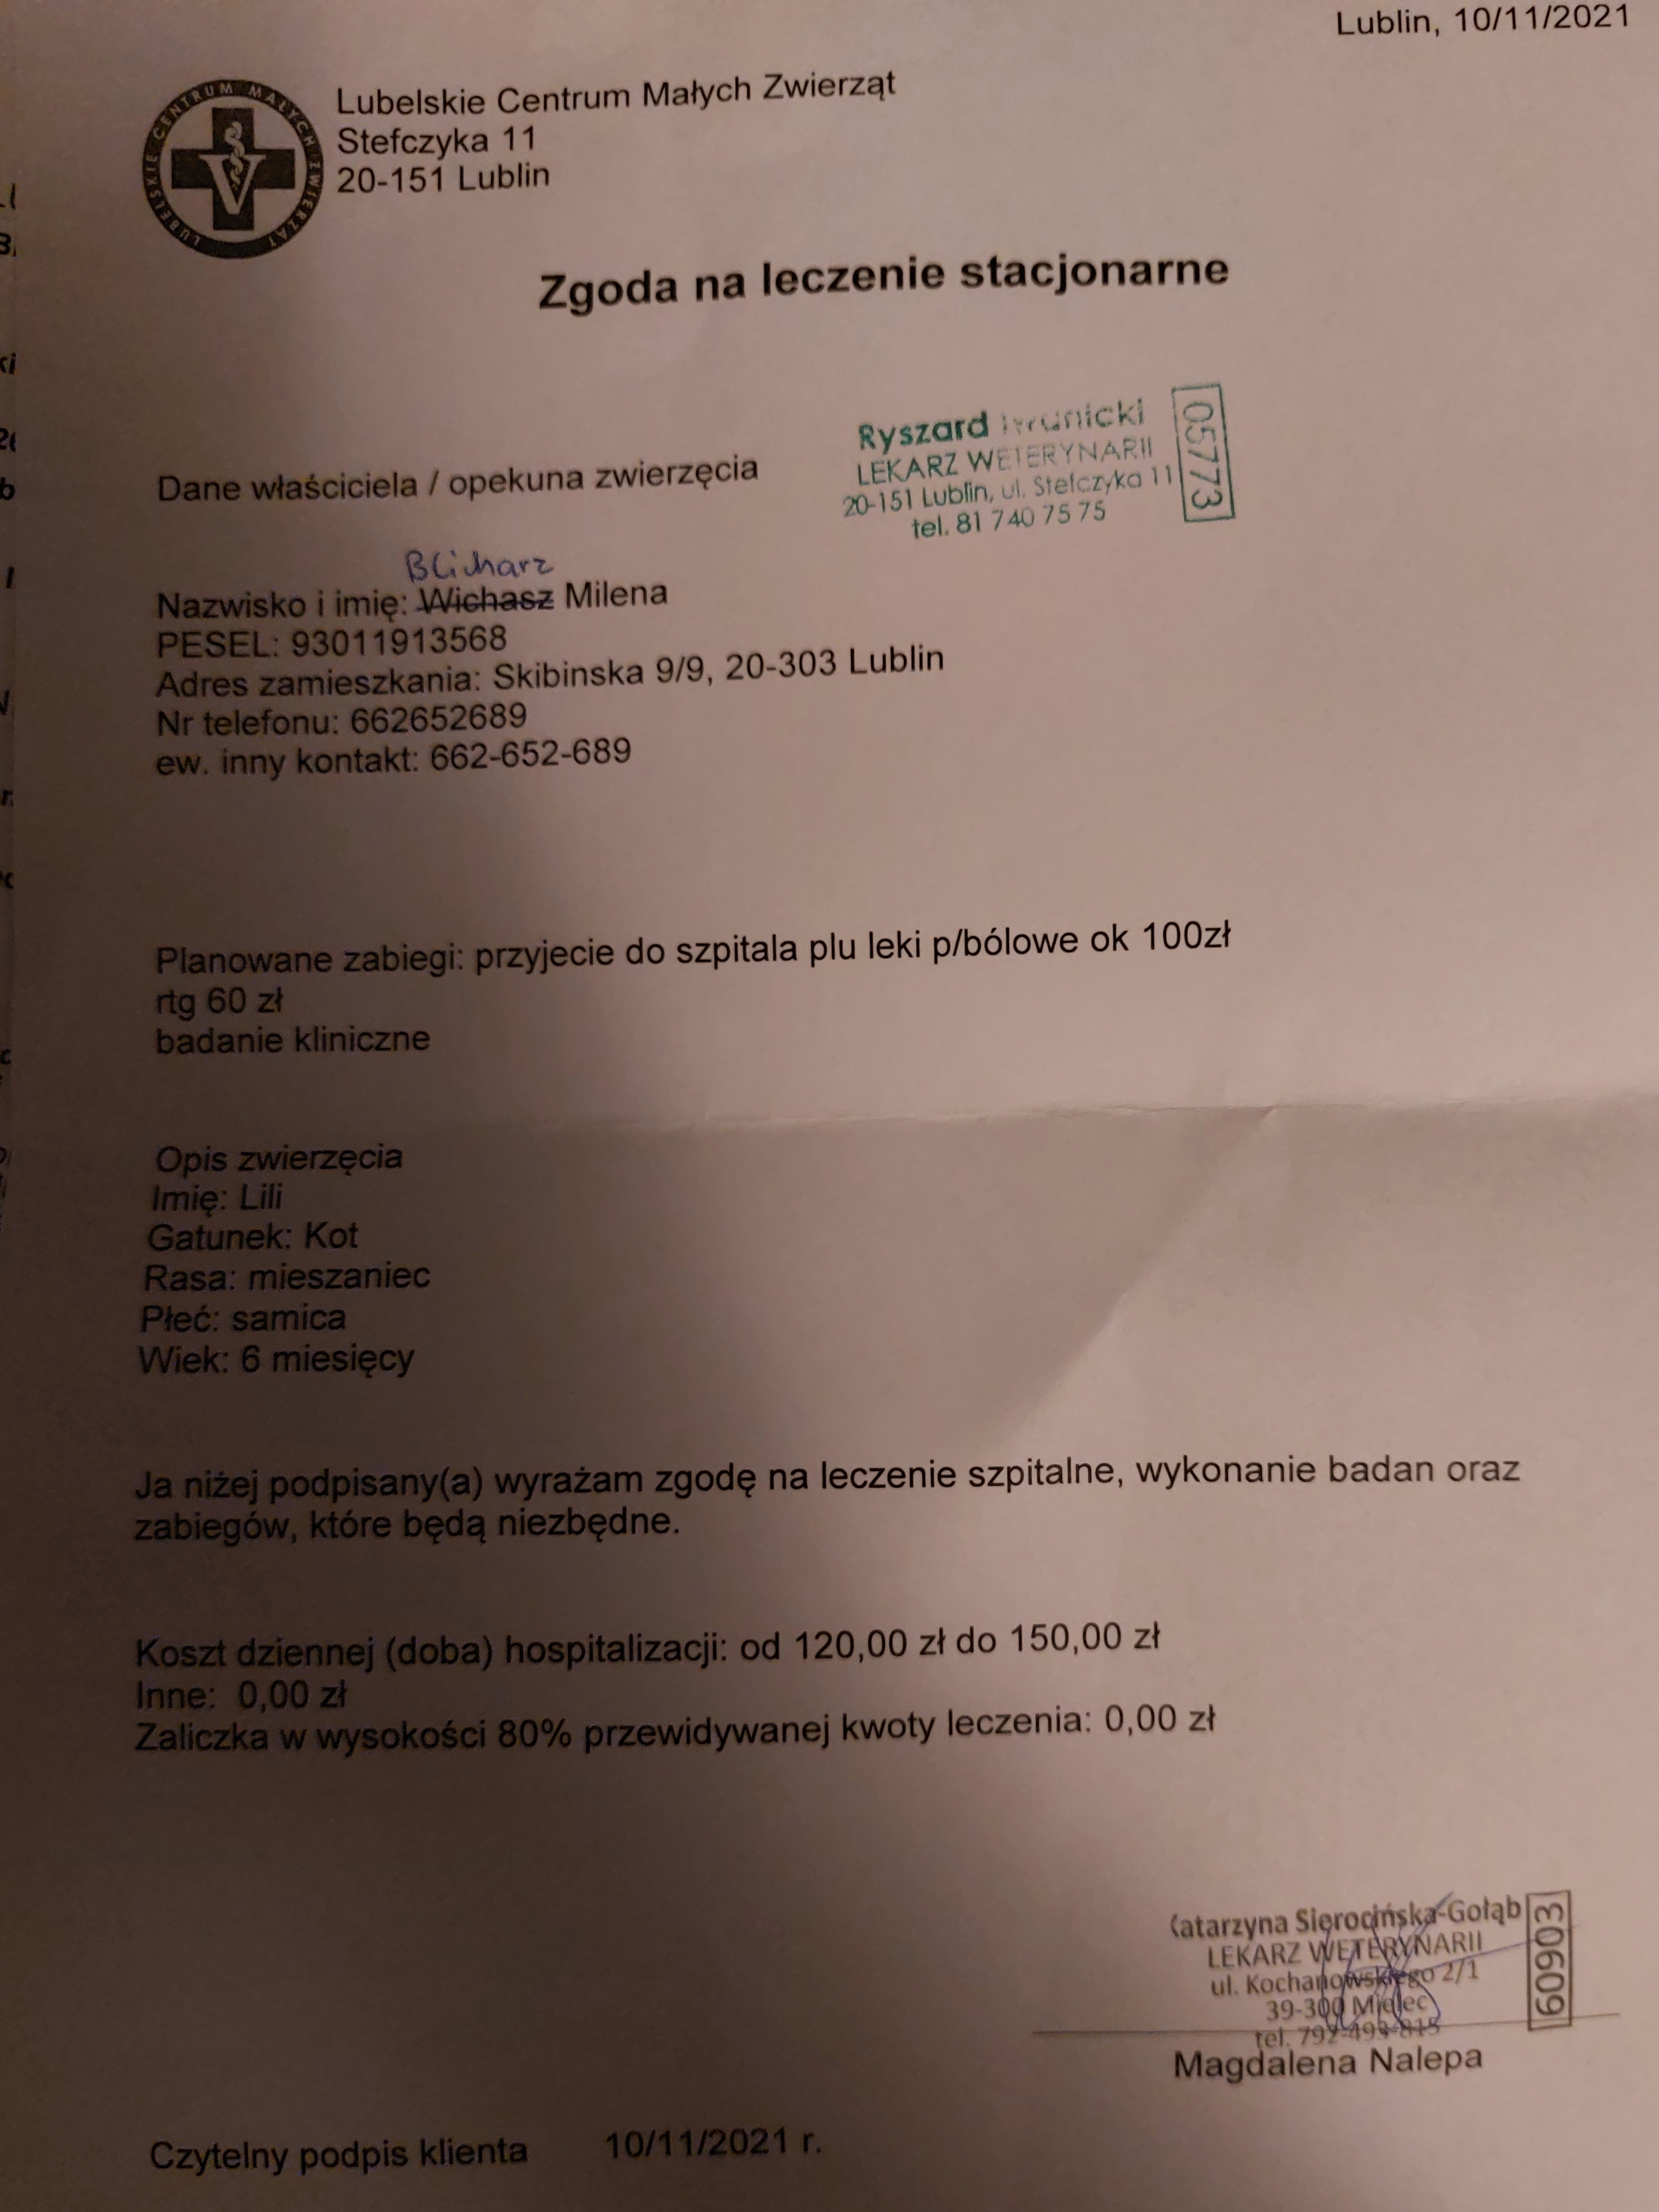

Moja kochana kotka LILI ma dopiero 6 mc a już tyle za nią.2 dni temu (10.11)zdażył się nieszczęśliwy wypadek i doznała urazu tzn konkretnie ma pęknięte lewą kość udową a prawe mocno potłuczone. Na dzień dzisiejszy od dwóch dni jest w klinice przy ul Stewczyka 11. W Lubelskim Centrum Małych Zwierząt. Lili potrzebuję operacji którą trzeba jak najszybciej zrobić, plan piątek (12.11) lub niedziela (14.11) .. A koszt jej to 1400zl. 10.11.2021 r. Lili trafiła do kliniki i do dnia dzisiejszego koszty badań i leków wyniósł około 500 zł.. bardzo proszę każdego kto ma możliwości i chęci pomóc o wpłacenie nawet najmniejszej kwoty, każda złotówka się liczy. Wiem że dla jednego to może i nieracjonalne że proszę o pieniądze na pokrycie kosztów leczenia ale niestety sytuacja mnie do tego zmusiła.. sama też nie jestem w dobrym stanie zdrowia i nie ukrywam że nie jest mi łatwo.. A ta kotka jest takim lekarstwem by choć trochę się trzymać na nogach. ( WIEM ŻE DUŻO OSÓB MOŻE NAWET NIE WIERZY, A DRUGICH TYLE TO WOGOLE NIE INTERESUJE)

Moja kochana kotka LILI ma dopiero 6 mc a już tyle za nią.2 dni temu (10.11)zdażył się nieszczęśliwy wypadek i doznała urazu tzn konkretnie ma pęknięte lewą kość udową a prawe mocno potłuczone. Na dzień dzisiejszy od dwóch dni jest w klinice przy ul Stewczyka 11. W Lubelskim Centrum Małych Zwierząt. Lili potrzebuję operacji którą trzeba jak najszybciej zrobić, plan piątek (12.11) lub niedziela (14.11) .. A koszt jej to 1400zl. 10.11.2021 r. Lili trafiła do kliniki i do dnia dzisiejszego koszty badań i leków wyniósł około 500 zł.. bardzo proszę każdego kto ma możliwości i chęci pomóc o wpłacenie nawet najmniejszej kwoty, każda złotówka się liczy. Wiem że dla jednego to może i nieracjonalne że proszę o pieniądze na pokrycie kosztów leczenia ale niestety sytuacja mnie do tego zmusiła.. sama też nie jestem w dobrym stanie zdrowia i nie ukrywam że nie jest mi łatwo.. A ta kotka jest takim lekarstwem by choć trochę się trzymać na nogach. ( WIEM ŻE DUŻO OSÓB MOŻE NAWET NIE WIERZY, A DRUGICH TYLE TO WOGOLE NIE INTERESUJE)